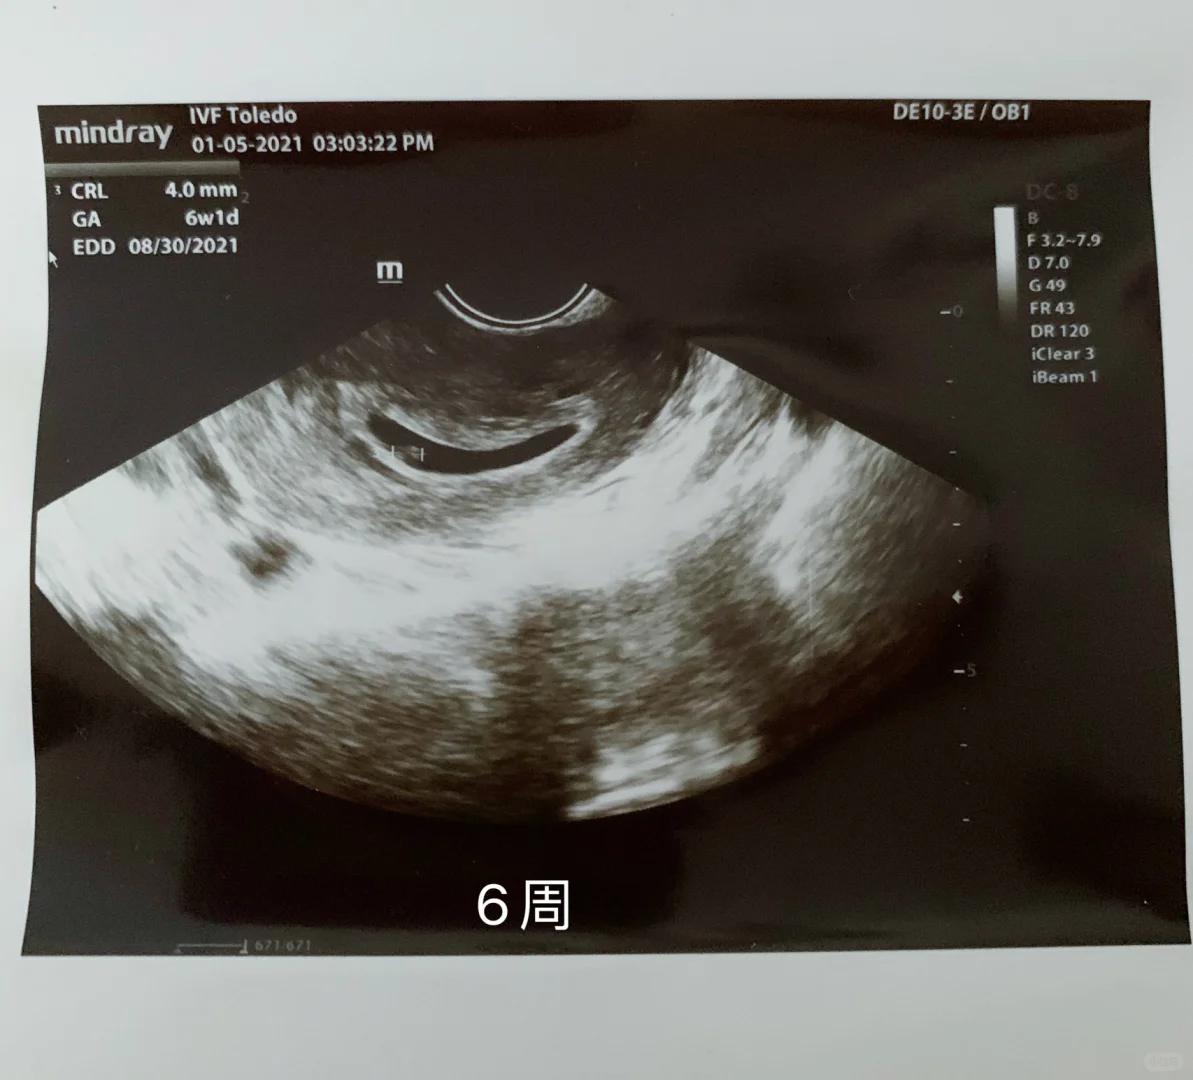

6周1月5日:圣诞节那天开party太操劳了,晚上开始有点褐色分泌物,之后的每一天量加多,粉色,白带有血丝,一直卧床休息……等了十天,2026年1月5日做第一次检查,宫内好孕,已经有6周+1天了……因为有一点宫腔积液,所以停止打肝素和阿司匹林……